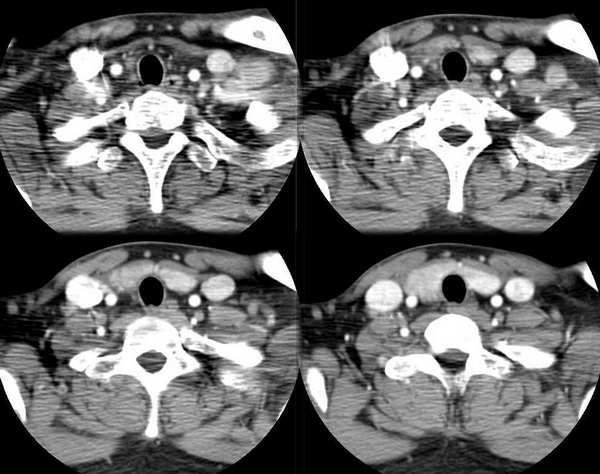

男,25岁,体温39.3度,发现右侧颈部包块.

右侧甲状腺内边界不甚清楚之占位,增强强化不很明显,无钙化。考虑腺瘤,建议活检,除外ca。

从片子上看考虑腺瘤可能性大,此病内有发热,急性炎症有除外。

此病例特点:1、年轻男性,基本上是高热;2、右侧甲状腺肿大呈边界不清之低密度,但甲状腺境界清晰;3、基本没有增强但低密度的周边略呈边缘增强反应;4、最好补充病史:痛否?时间?(如痛、急性起病。)

据此,以甲状腺急性炎症可能性大。